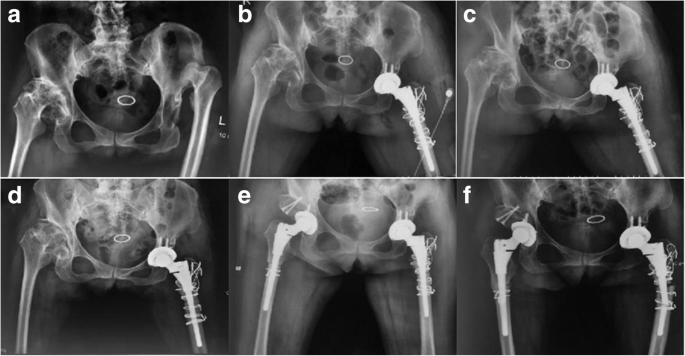

A 52-year-old woman with bilateral DDH (Fig. 1a) underwent left and right THA with subtrochanteric osteotomy at a local hospital in November 2016 and February 2017, respectively. The bilateral stem was a modular hip system (Just company, China, imitation of S-ROM). The patient felt no pain in the hip and performed normal activities after the operation. Postoperative follow-up X-ray examination revealed that the osteotomy area of the left femur had not healed (Fig. 1b–e). No further treatment was administered. The patient denied a family genetic history. In October 2017, the patient experienced spontaneous left-sided thigh pain when bearing weight. She was very frightened, and could neither stand on both legs or walk. The movement of the left hip joint was limited, and the patient could not participate in social activities or even care for herself. Therefore, she came to our hospital for treatment. Physical examination revealed tenderness of the left thigh and a limited movement of the left hip joint (0–90° in extension-flexion). A radiographic image showed a fracture in the distal part of the stem and revealed that the subtrochanteric osteotomy site of the left femur had not healed (Fig. 1f). Laboratory examination was not suggestive of an infection (white blood cell count: 4.52 × 109/L; erythrocyte sedimentation rate: 6 mm/h; C-reactive protein level: 6.26 mg/L; neutrophil percentage: 64.9%). She was diagnosed with a modular prosthesis fracture, and we performed a revision surgery. The acetabular component was not revised, because a preoperative X-ray examination and intraoperative findings revealed a well-fixed acetabular component. The proximal stem and sleeve were removed using an extractor and osteotomes, and the bone growth of the removed sleeve was found to be good. The fractured prosthesis was removed using the window technique (Fig. 2a–b). A fully-coated revision stem (200 mm in length, 9 mm in diameter; Chung-Li company, China) was implanted after reduction of the fracture, and the proximal femoral bone defect was reconstructed using a cortical bone plate (Xin-Kang-Chen company, China) (Fig. 2c). The catheter was removed 24 h after the operation. Antibiotics were injected intravenously for 3 days after the revision surgery, while anticoagulants were administered orally until 35 days after the operation. Following the principle of moving from easy and passive exercises to difficult and active exercises, the patient performed muscle strength and joint mobility exercises for the left limb in the early stages and hip function and gait exercises in the later stages. Partial weight-bearing was allowed 7 days after the operation, and completely weight-bearing was allowed 4 weeks after the operation. The patient was followed up via outpatient examinations. During the follow-up period, the patient’s condition gradually improved. One year postoperatively, the patient felt no pain and could walk normally. The left hip joint movement was not restricted. The patient could take care of herself, and was able to perform all of her activities of daily living. The visual analogue scale score and the Harris Hip score significantly improved from 7 and 48 preoperatively to 2 and 85 1 year postoperatively, respectively. The patient was very satisfied with the therapeutic effect. Plain radiographs showed union in the subtrochanteric osteotomy site of the left femur (Fig. 3).

Radiographic images before revision surgery (a-f). a Crowe type IV DDH was found at the left hip before primary surgery. b-e Radiographic images of the patient’s left primary THA 1 day, 1 month, 3 months, 5 months postoperatively. f The radiographic examination of the patient’s left primary THA 14 months postoperatively shows that the distal stem is broken and the subtrochanteric osteotomy of the left femur is not healed